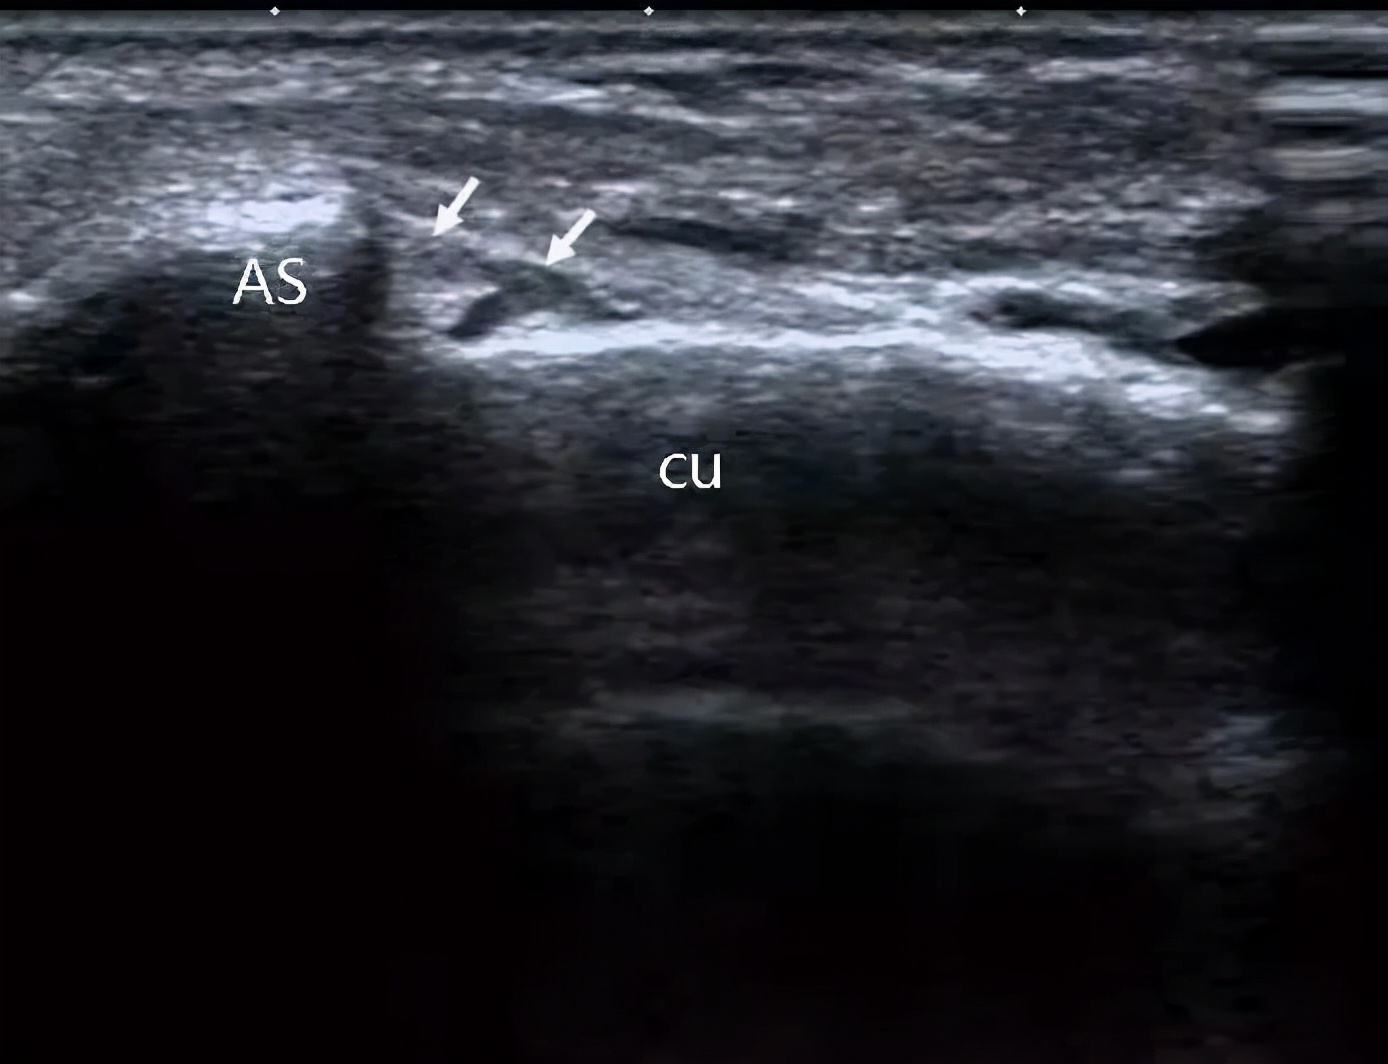

肌骨彩超提示:右侧颈7横突与颈肋相连,右侧臂丛神经下干受压。

就是彩超诊断这个大爷多了根肋骨,这根多的肋骨压迫到神经,导致了手麻。然后大爷再去拍了x片和磁共振,进一步证实了超声的诊断。

红线描绘出肿胀受压的臂丛下干